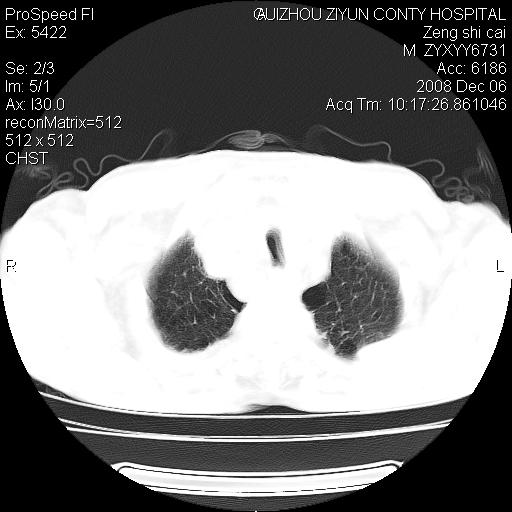

标题: CT16961:M、71岁,咳嗽半年,无血痰;胸片示右肺占位。 [打印本页]

标题: CT16961:M、71岁,咳嗽半年,无血痰;胸片示右肺占位。

右肺癌并纵隔淋巴结及胸膜转移可能性大

右肺癌并纵隔淋巴结及胸膜转移。建议气管镜

右肺纵隔型肺癌伴纵隔淋巴结及胸膜转移!

右肺纵隔型肺癌伴纵隔淋巴结转移!双侧胸水!

1)考虑右肺上叶纵隔型肺癌伴纵隔淋巴结转移。2)心包积液,双侧胸腔积液。

右肺癌并纵隔淋巴转移,腹膜后转移可能性大,两侧胸腔积液

右肺上叶纵隔型肺癌伴纵隔淋巴结转移。心包积液,双侧胸腔积液。

右上肺癌并纵隔淋巴结及胸膜转移。

右肺纵隔型肺癌伴纵隔淋巴结转移!双侧胸水\\心包积液

建议强化!主要鉴别是淋巴瘤与肺癌淋巴结转移。

右肺纵隔型肺癌伴纵隔淋巴结及胸膜转移